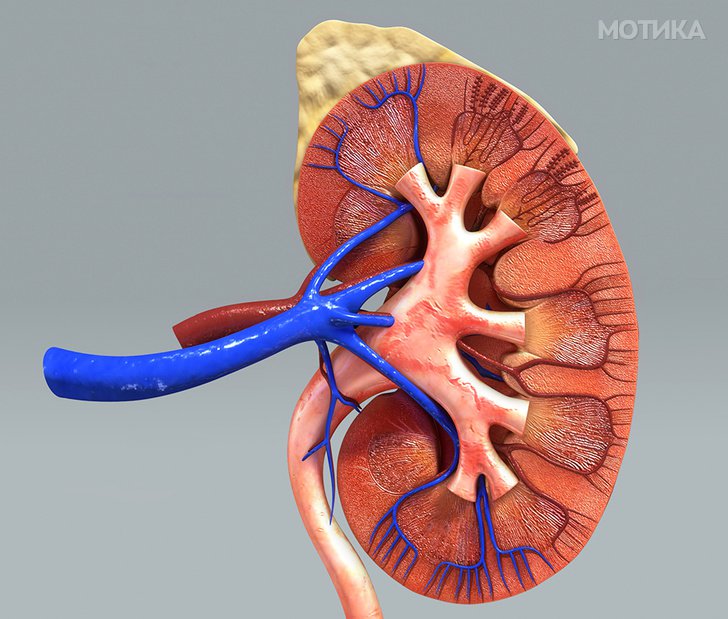

4. Бубрези

- Главната функција на бубрезите е да се прочисти крвта од отпадни производи. И за да успее во тоа, секој поединечен бубрег има најмалку еден милион и до 2 милиони специјални мали филтри, наречени нефрони.

- Навистина не ни требаат 2 бубрези, половина од една може да завшри исто толку добра работа како 2.

- Ако детето е родено со само еден бубрег, тоа ќе се здебели до тежината на 2 бубрези.